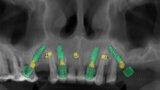

Compromised maxillary dentition treated with Straumann Pro Arch and a digital workflow